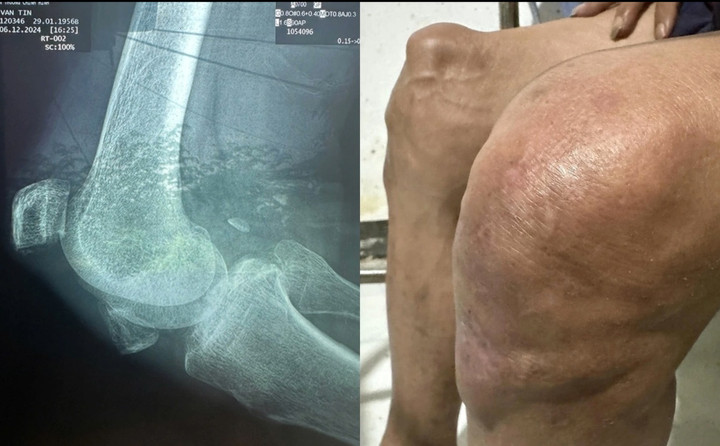

Hiện tại, sức khoẻ của Thương Tín ngày càng suy yếu. Diễn viên đã mất khả năng đi lại, phải ngồi xe lăn hoặc nhờ người ẵm bồng. Theo kết quả của bác sĩ, chân phải của ông bị bể đôi bánh chè, không còn khả năng hồi phục. Chân trái bị viêm khớp gối nặng, cần uống thuốc điều trị lâu dài.

Thương Tín bị viêm khớp gối nặng.